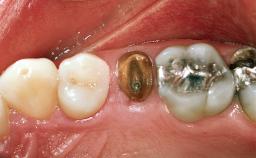

Replacement of the Four Maxillary Incisors with a Fixed Dental Prosthesis Using an Immediate Loading Protocol

In November 2001, a 53-year-old female presented seeking advice and options for treatment of her maxillary incisor teeth. She was dissatisfied with both the functional and esthetic qualities of her existing restorations. Her medical health was excellent, and she reported no contraindications to dental care. On presentation, the patient’s dental health was less than ideal. Although she had no probing depths greater than 3 mm, she suffered from generalized chronic adult periodontitis and displayed multiple sites of bleeding on probing. Her remaining dentition was heavily restored, and many teeth had been endodontically treated. Areas of recurrent dental caries were noted on many teeth. Radiographically and clinically, the maxillary incisor teeth exhibited large areas of active caries, and after the splinted crowns had been removed, the teeth were determined to be non-restorable.